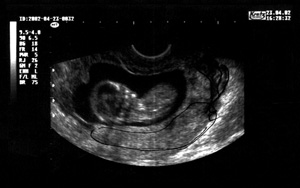

Εικόνα 1: Υπερπλασία ενδομητρίου. Εικόνα 2: Κύηση 13 εβδoμάδος. Αποκόλληση πλακούντα.

Κατά τον κολπικό υπερηχογραφικό έλεγχο ανευρίσκεται κύηση ζώντος εμβρύου χωρίς εμφανείς ανωμαλίες με υπερηχογραφική ηλικία κύησης περίπου 13 εβδομάδων και μικρή αποκόλληση του πλακούντα (εικ. 2).